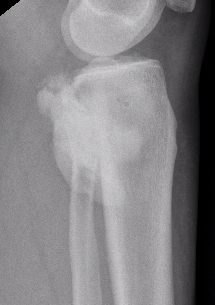

Parosteal Osteosarcoma proximal tibia

# Cortical tumors of posterior femur should be considered malignant #